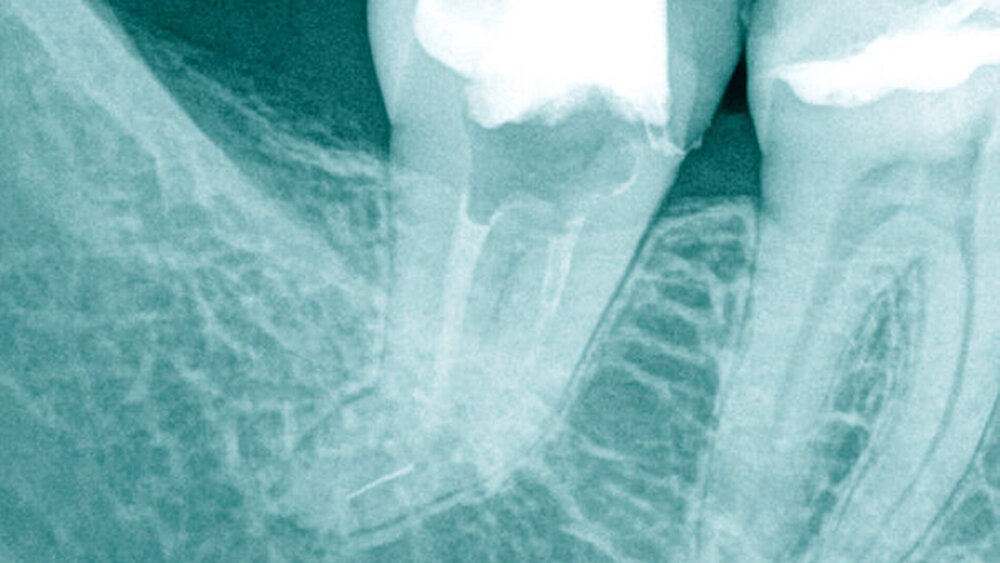

Fallbeispiel 1 (Abbildung 1)

Aufgrund einer fortbestehenden mikrobiellen Infektion wurde eine endodontische Revision am Zahn 26 erforderlich. Unter vergrößerter Sicht mit einem Dentalmikroskop ließen sich drei in Einstifttechnik gefüllte Wurzelkanäle bei achtfacher Vergrößerung darstellen. Am Boden der Pulpakammer ist das Primärdentin von dem die Pulpakammer einengenden Sekundärdentin zu differenzieren, so dass unbehandelte endodontische Hohlräume gut erkannt werden können (Abbildung 1a).

Im Verlauf des minimalinvasiven Abtrags von Sekundärdentin mit Langschaftrosenbohrern in absteigender Größe 012 bis 005 gelingt es, den zweiten Anteil des mesiobukkalen Wurzelkanalsystems (MB2) für eine mechanische Erweiterung, Reinigung und Desinfektion freizulegen (Abbildung 1b). Im Verlauf der Präparation des distobukkal teilweise gefüllten Wurzelkanals wird die Diskrepanz zwischen bisher aufbereitetem Volumen und tatsächlicher Dimension des Wurzelkanalsystems deutlich. Die Fusion der distobukkalen mit der palatinalen Wurzel hinterließ ein langgestrecktes, bandförmiges Wurzelkanalsystem mit fibrosierten und kalzifizierten nekrotischen Geweberesten (Abbildung 1c).

Unter kontinuierlicher mikroskopischer Kontrolle erfolgte die mechanische Erweiterung mit rotierenden NiTi-Instrumenten, so dass eine Desinfektion und eine vollständige thermoplastische Wurzelkanalfüllung möglich wurden (Abbildungen 1d und 1e).